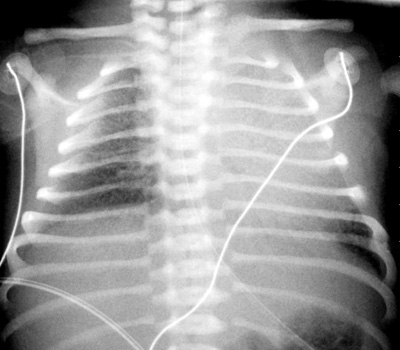

1: The appropriate position of the UAC is at the level of the diaphragm.